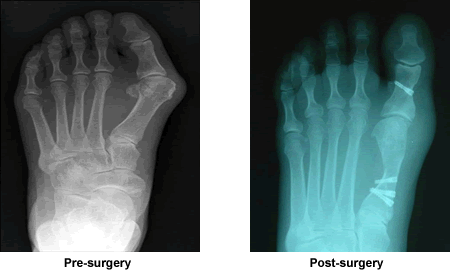

I would like to thank Dr. Leavitt tremendously for the wonderful surgery he did on my foot. He is such an expert surgeon coupled with human touch and professionalism. I'm fortunate to have him as my surgeon, and it is encouraging to know that I will be able to walk straight again in due time. And I appreciate that he sent me those x-rays... How interesting to see what's actually inside my little foot.